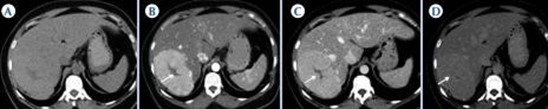

La hiperplasia nodular focal es el segundo tumor benigno más frecuente después del hemangioma. Tiene mayor incidencia en mujeres jóvenes. Histológicamente es un tumor hiperplásico que conserva los mismos componentes del tejido hepático normal, pero con una arquitectura alterada (hepatocitos normales + células de Kupffer + conductos biliares primitivos no conectados con la vía biliar normal). Presentan una cicatriz central de tejido fibroso con estructuras vasculares dilatadas y ectásicas. En la tomografía multicorte sin contraste intravenoso se evidencia como una lesión homogénea bien definida, hipo o isodensa con respecto al parénquima hepático. En la tomografía multicorte multifásica, después de la administración del medio de contraste, tiene un comportamiento típico.

- Fase arterial: reforzamiento intenso.

- Fase portal: es isodenso o ligeramente hiperdenso con respecto al parénquima.

- Fase tardía: lesión totalmente isodensa, no se visualiza, excepto porque puede producir efecto de masa sobre el parénquima adyacente.

La cicatriz central (Anexos 21 y 22), al estar menos vascularizada, no refuerza en fase arterial. Sin embargo, en fase tardía muestra hiperdensidad cuando ya el resto de la lesión se ha hecho isodensa.(18)

Son tumores poco frecuentes. Histológicamente están formados por hepatocitos bien diferenciados sin conductos biliares ni triada portal (tumor formado exclusivamente por hepatocitos). Pueden presentar áreas intralesionales de necrosis y de hemorragia. Es más frecuente en las mujeres (90%) que toman anticonceptivos orales y en hombres que toman esteroides anabólicos, así como en pacientes con enfermedades por depósito (glucogenosis tipo 1 o diabetes).

Actualmente los adenomas se clasifican en tres subgrupos, dependiendo de su genotipo.(18) Es importante la clasificación para poder establecer su comportamiento, hallazgos por imagen, historia natural y, sobre todo, un riesgo variable de presentar complicaciones como hemorragia o malignización. Por ende, según sea el subtipo, también difiere el tratamiento. En la tomografía multicorte, en fase sin contraste, se observan como lesiones bien definidas, isodensas o ligeramente hipo o hiperdensas con respecto al parénquima (Anexo 23). Pueden presentar una densidad heterogénea o áreas de hemorragia.

En las fases dinámicas, tras la administración de medio de contraste,(18-24) son lesiones hipervasculares, ya que muestran importante reforzamiento en fase arterial. En las fases venosas portal y tardía se pueden diferenciar según el subtipo como: adenoma inflamatorio: persistencia del reforzamiento; adenoma HNF1A mutado: que se observa isodenso con respecto al parénquima normal; beta catenina mutada: que es hipervascular en fase arterial con lavado del medio de contraste similar al carcinoma hepatocelular.(18-20-24)